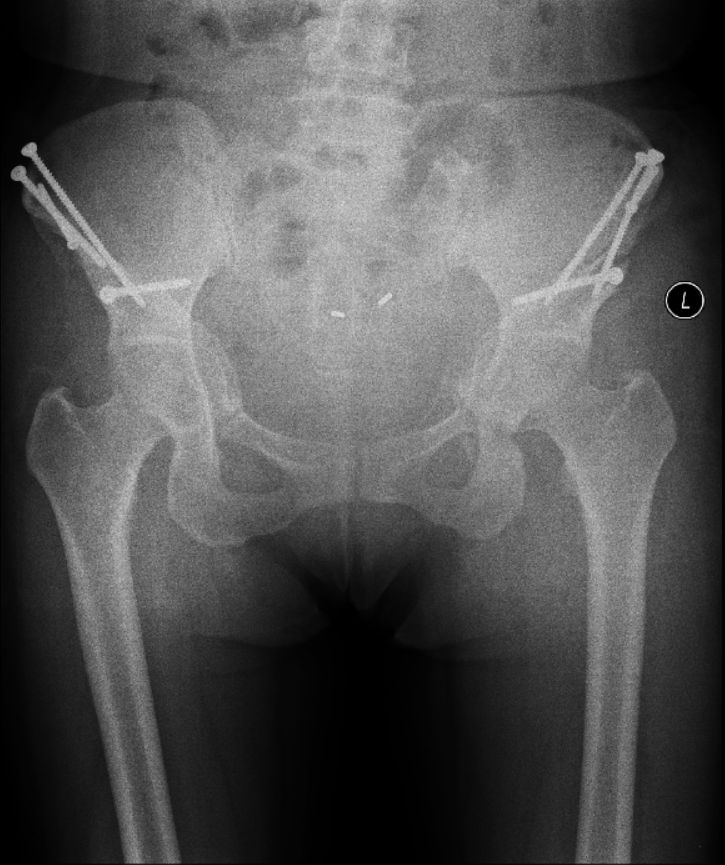

2018-11 髋臼PAO截骨术后第3天:双髋关节正位X线片

2019-09 左侧髋臼PAO截骨术后第3天:双髋关节正位X线片,右侧术后10个月

2020-01 左侧髋臼和股骨近端上下PAO截骨术后第3天:双髋关节正位X线片